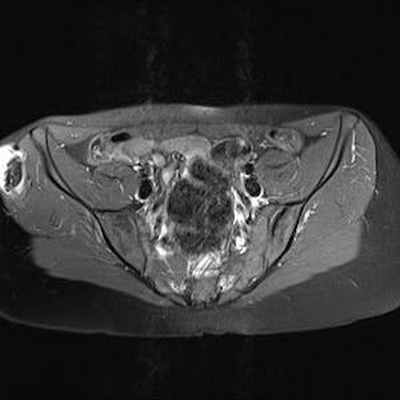

МРТ: чётко видимая хрящевая шапочка, имеющая геперинтенсивный сигнал на T2 (DP)-ВИ и изоинтенсивный сигнал на Т1-ВИ, неправильной формы и очень плотная (23 мм), принимающая дольчатый вид, вызывающая подозрение на саркоматозную дегенерацию. Периферическое повышение сигнала после инъекции.

IRM Pelvis Axial Pondération DP

IRM Pelvis Axial Pondération T1gadolinium fat sat